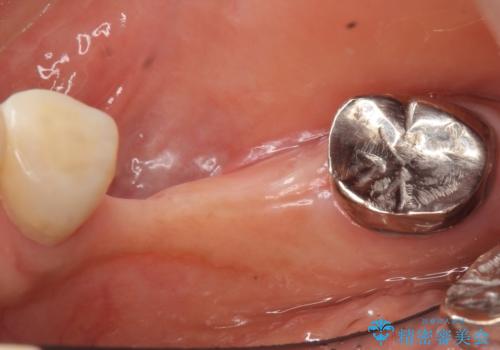

- 奥歯のインプラントをご希望され、来院された患者様です。

骨が薄いため、他院ではインプラントできないと言われたとの事でした。

精査したところ、右下4の根尖病変及び右下5の欠損を認め、右下6は残根となり保存不可能な状態でした。